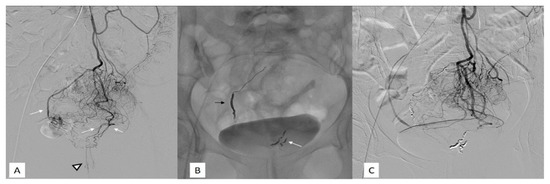

5. Arterial Anatomy

- Type II: the main trunk passes to the right, giving off branches to the left.

- Type III: the main trunk passes to the left supplying branches to the right and a MRA define a relevant contribution to the vascularization of the CCR.

- Type IV: trifurcation of the main trunk with supplying branches to both sides of the anal canal in some with a minor participation of MRA to the vascularization of the CCR (Figure 2).

- Type V: trifurcation of the main trunk with supplying branches to both sides of the rectum not reaching the anal canal with an MRA defining a main contribution to the supply of CCR.